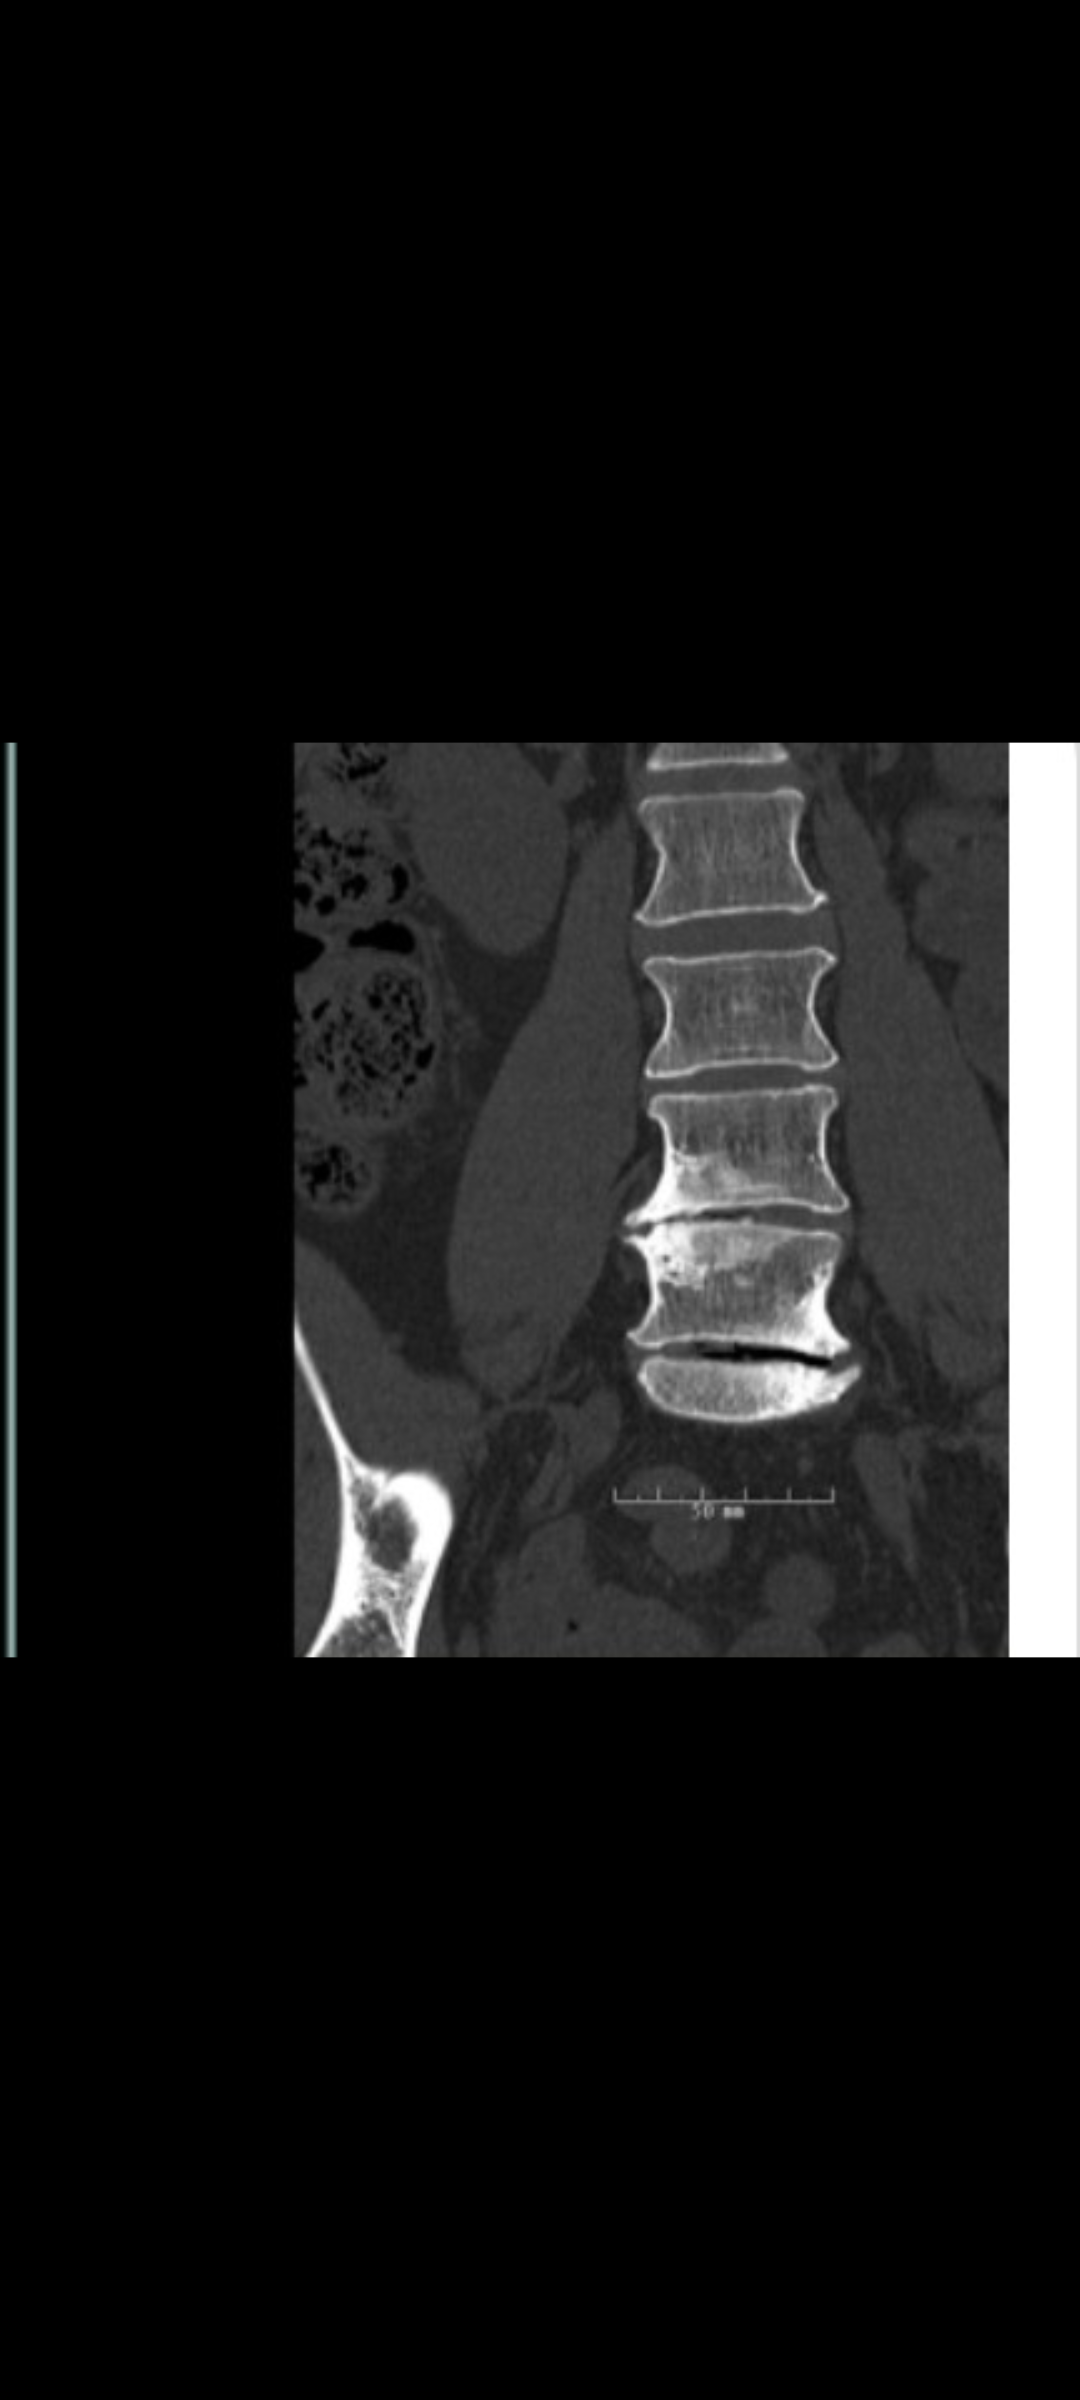

I’ve been diagnosed with degenerative disc disease and spinal stenosis, which have caused years of chronic pain and nerve compression.

Those falls accelerated everything. What was once “eventually” became “as soon as possible.” Since then, I’ve been undergoing a nerve ablation series in my cervical spine to help manage the upper spine and neck pain while preparing for the lumbar spinal fusion (L4–S1) scheduled for December 18, 2025, at Rush University Medical Center.